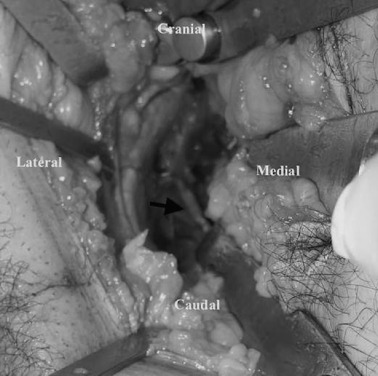

PAO was performed as originally described; however, the exposure involved a modified Stoppa incision. The cadavers were laid supine on a radiolucent operating table, and a 10-cm transverse incision was made 2 cm above the symphysis pubis (Fig. 1 ). The rectus sheath was carefully incised at the inferior border of the rectus abdominis muscle. After incision of the fascia transversalis, the abdominal muscles were bluntly dissected, and the peritoneum was retracted craniomedially with a blunt retractor. The psoas and iliac veins lying on the linea pectinealis were dissected bluntly and retracted carefully. The corona mortis was dissected carefully (Fig. 2 ). The periosteum was raised above the iliopectineal line, and a blunt retractor was inserted into the greater sciatic notch. At this stage, the obturator nerve was visualized in all cases and carefully preserved (Fig. 3 ).

The obturator nerve. The obturator nerve (white arrow), which is prone to injury ...

Fig. 3.

The obturator nerve. The obturator nerve (white arrow) , which is prone to injury in modified Stoppa approach, was dissected and protected.